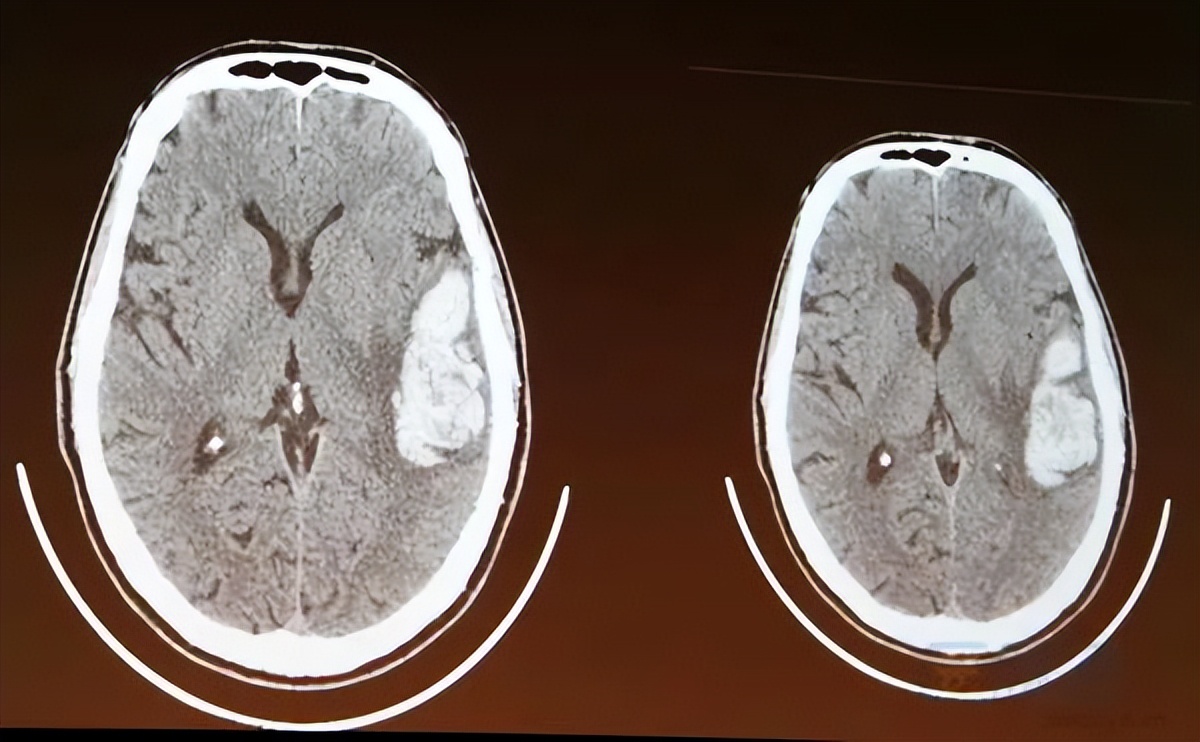

脑出血的CT表现

脑出血的诊断 一般需要到医院做头颅CT检查。若CT检查发现脑内有异常高密度影,就可以明确诊断是脑出血。CT检查同时可以出血部位,如脑实质内,脑室内、硬膜外/下,蛛网膜下腔等,进而辅助判断原因,这时有时需行头颅磁共振或者头颅CT/MRA/DSA血管造影等相关检查。同时还可根据出血的形态,判断再出血的可能。